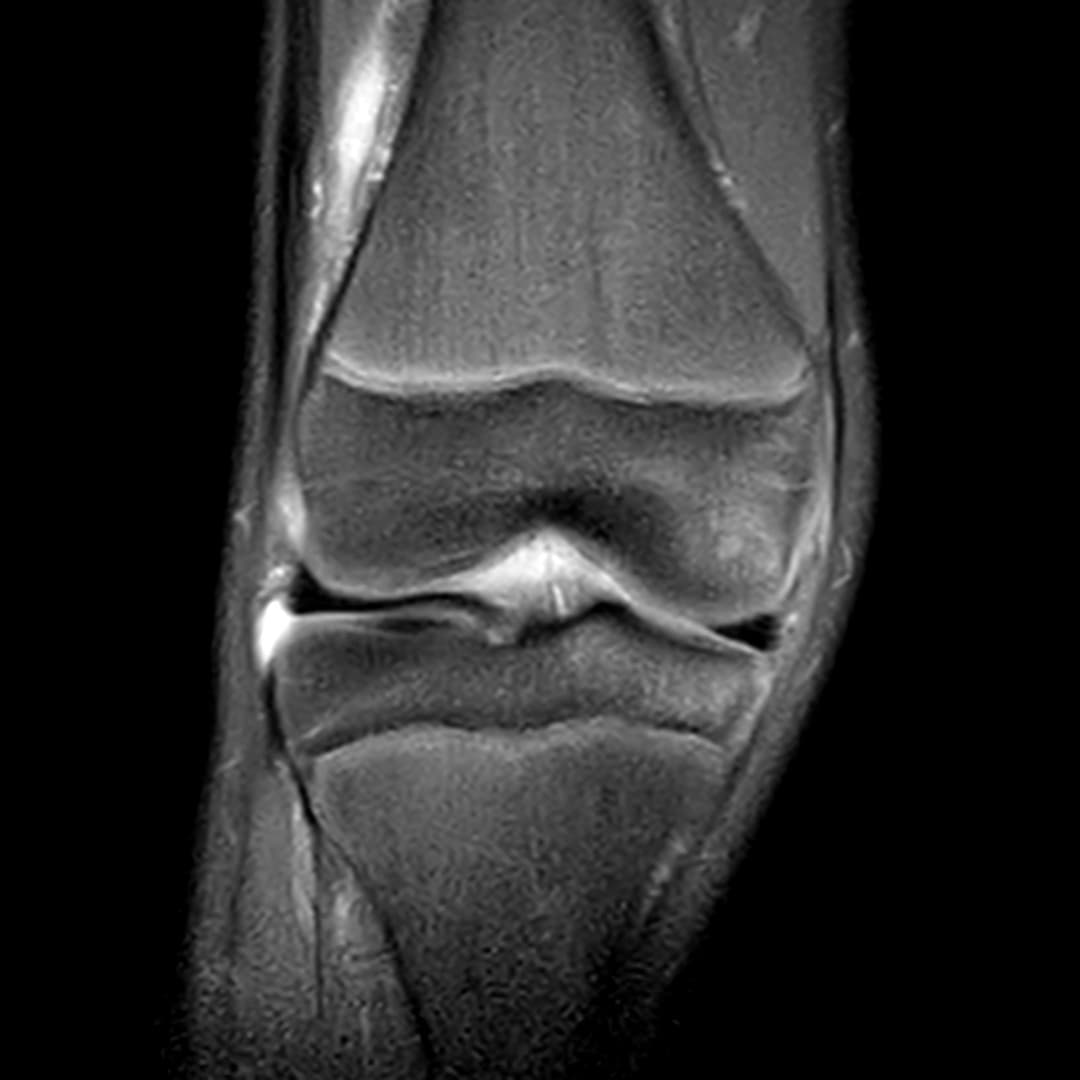

Contusion osteo-chondrale du genou

IRM

Intégrité ligamentaire et méniscale

Fracture sous chondrale par impaction avec œdème sous chondral en miroir du compartiment fémoro-tibial médial.

Epanchement articulaire abondant.